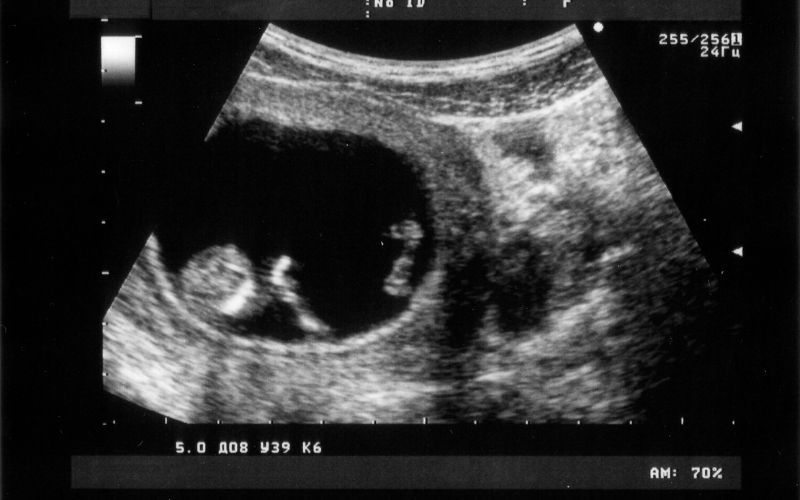

Siêu âm

Siêu âm là phương pháp chẩn đoán hình ảnh sử dụng sóng âm để tạo ra hình ảnh của các cơ quan bên trong cơ thể. Trong trường hợp IVF, siêu âm được sử dụng để xác định xem thai đã vào tử cung hay chưa và đánh giá sự phát triển ban đầu của thai nhi.

Thời điểm siêu âm:

Siêu âm thường được thực hiện khoảng 5-6 tuần sau khi chuyển phôi, khi thai đã đủ lớn để có thể nhìn thấy trên siêu âm.

Các loại siêu âm:

- Siêu âm đầu dò âm đạo: Đầu dò siêu âm được đưa vào âm đạo để có hình ảnh rõ nét hơn của tử cung và buồng trứng.

- Siêu âm bụng: Đầu dò siêu âm được đặt trên bụng để tạo ra hình ảnh.

Mục đích của siêu âm:

- Xác định vị trí thai: Đảm bảo thai nằm trong tử cung (loại trừ thai ngoài tử cung).

- Xác định số lượng thai: Xác định xem có phải là đơn thai hay đa thai.

- Đánh giá sự phát triển của thai: Đo kích thước túi thai và phôi thai để đánh giá sự phát triển ban đầu.

- Kiểm tra tim thai: Tìm kiếm tim thai để xác định thai có còn sống hay không.